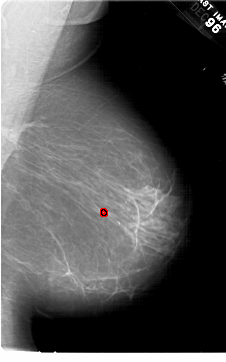

A_1452_1.LEFT_CC

LEFT_CC LINES 6376 PIXELS_PER_LINE 3676 BITS_PER_PIXEL 12 RESOLUTION 43.5 NON_OVERLAY

FILE: A_1452_1.RIGHT_MLO.OVERLAY

TOTAL_ABNORMALITIES 1

ABNORMALITY 1

LESION_TYPE CALCIFICATION TYPE PLEOMORPHIC DISTRIBUTION CLUSTERED

ASSESSMENT 4

SUBTLETY 4

PATHOLOGY BENIGN

TOTAL_OUTLINES 1

BOUNDARY